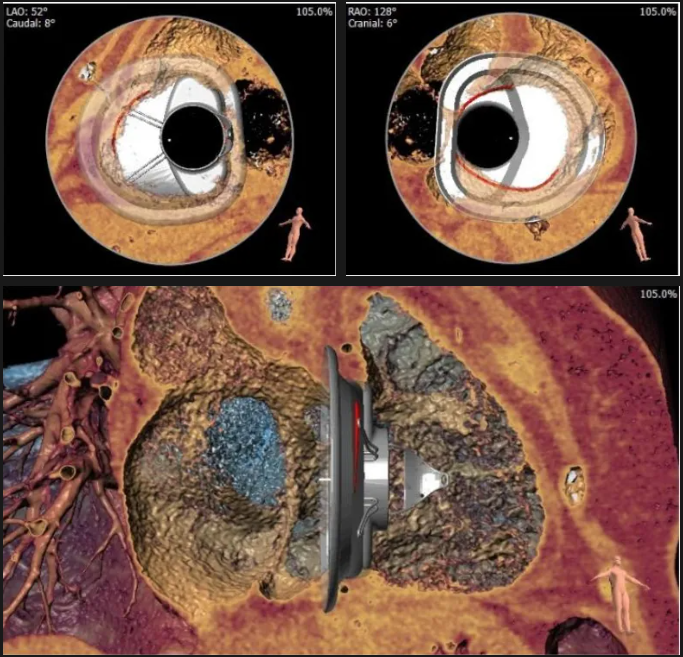

術(shù)前心臟CT評估

三尖瓣環(huán)平均周長徑54.3mm,最大直徑57mm

心房側(cè)周長平均徑(封堵高度)74.0mm

三尖瓣環(huán)切線位夾角 103°

術(shù)前術(shù)后返流情況對比